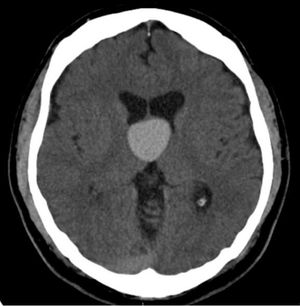

Colloid Cysts

ByRaquel Bezerra, MD,Erini Makariou, MD

A 38-year-old male presents with headache.